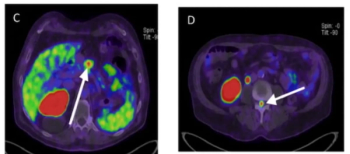

In a cohort of 85 patients with biomechanical recurrence of prostate cancer and PSA values less than 2 ng/mL, positive findings on PET imaging with PSMA-18F DCFPyL led to treatment changes in the majority of patients who had negative findings on conventional imaging, according to new research presented at the SNMMI conference.